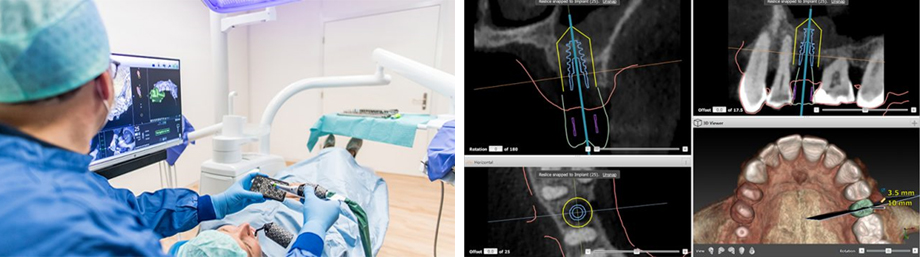

Le X-Guide est un système de navigation en 3D pour le chirurgien, rendant la pose d’implants dentaires plus précise et sécuritaire que jamais auparavant.

Le chirurgien voit dorénavant en temps réel l’axe d’implantation et la profondeur de l’implant, ce qui lui permet de s’assurer que l’implant est placé exactement comme il l’avait planifié.

Il s’agit d’un GPS pour chirurgien qui lui permet de suivre la voie tracée !